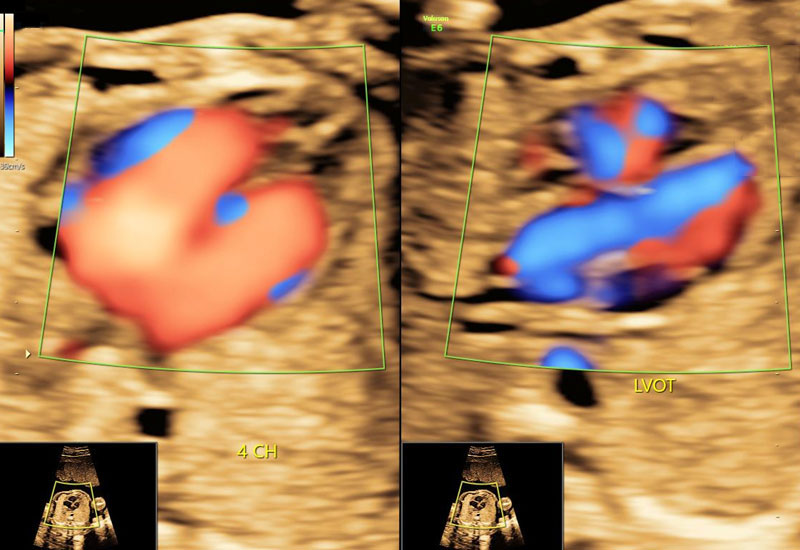

Fetal Echocardiography is a targeted ultrasound that evaluates the structure, function, and blood flow of the fetal heart. Unlike routine scans, this test focuses exclusively on identifying congenital heart abnormalities in detail.

- Four-chamber view of the fetal heart

- Outflow tracts of major vessels

- Blood flow patterns using Doppler